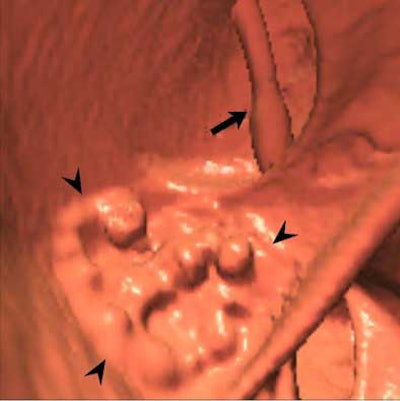

His father's surgery went smoothly, Pickhardt told AuntMinnie.com the next day. And the patient, an otherwise-healthy 65-year-old, was kind enough to allow images of the 5-cm lobulated rectal "carpet" lesion to be included in this article.

| In an asymptomatic 65-year-old male patient, 3D endoluminal view in virtual colonoscopy shows lobulated "carpet" lesion in rectum (arrowheads, above). The top arrow indicates the rectal catheter. Same-day conventional colonoscopy shows the endoscopic view of the same lesion (below). Same-day endorectal ultrasound (as part of conventional colonoscopy) shows a broad superficial lesion along the rectal wall with no evidence of bowel-wall invasion (bottom). The biopsy showed villous adenoma with high-grade dysplasia; histological results are pending. All images courtesy of Dr. Perry Pickhardt. |